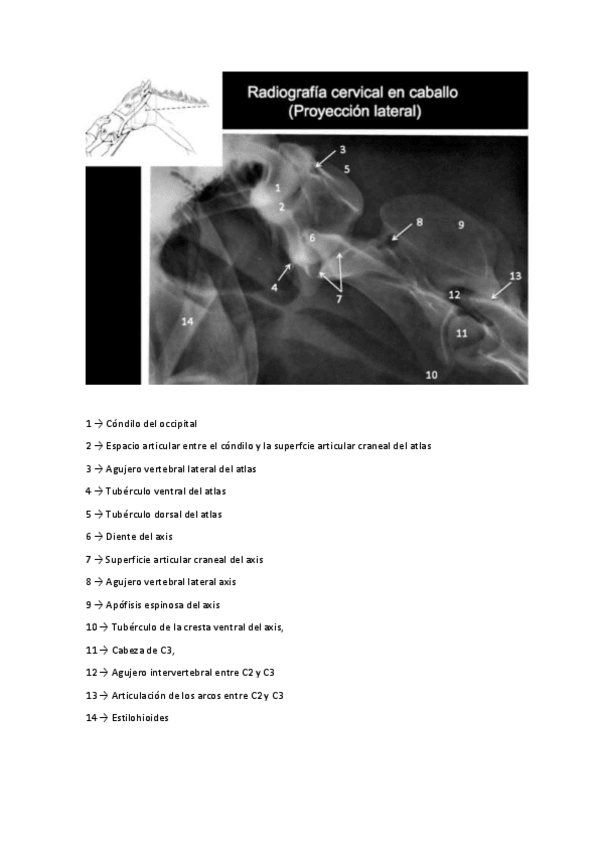

Apuntes - Esquemas-de-anatomia.pdf

Apuntes - Todas-las-radiografias.pdf

Apuntes - Todas-mis-radiografias-resueltas.pdf